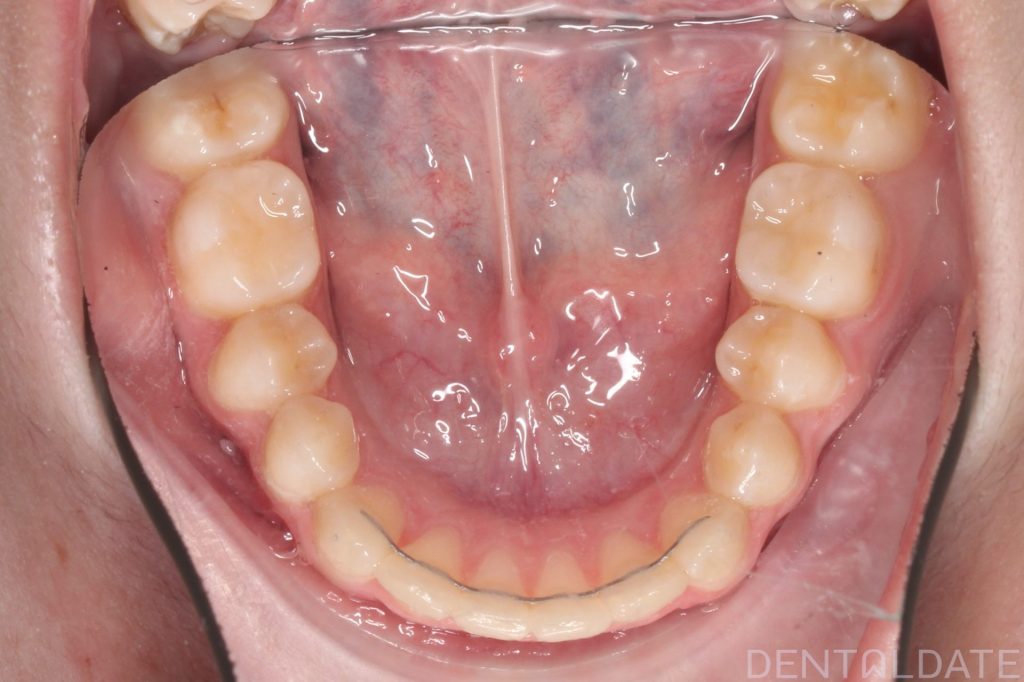

One tooth had erupted palatelly, with no space available for it in the dental arch.

The central aesthetic lines did not match, and the bite was incorrect.